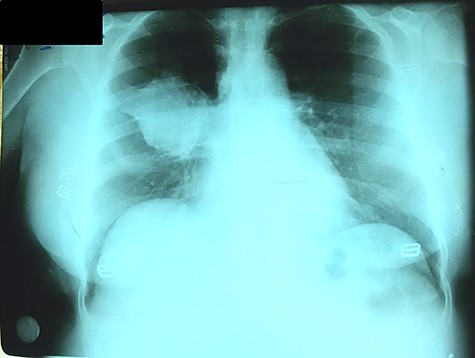

Chest X-ray (CXR) showed a heterogeneous density with irregular margins in the right lung (Fig. 1). CT scan demonstrated a heterogeneous mass that measured 5.5 × 6 × 7.8 cm with irregular thick margins. The mass was anteriorly located in the upper lobe of the right lung with air bubbles and necrosis (Fig. 2). Two lymphadenopathies were observed that measured around 2 cm each; one of which was in the hilum of the right lung and the other was located inferior to the right main bronchus. No other lesion was detected elsewhere. PET scan was also suggestive of malignancy as it demonstrated a heterogeneous mass with irregular margins which had irregular enhancement in the peripheral, suggesting hyper metabolic retention. The standardized uptake values (SUV) of the mass ranged between 4 and 7 with central necrosis and multiple gas bubbles. Multiple lymphadenopathies were also observed with different sizes ranged from 10 to 20 mm with SUVmax reaching 7 (Fig. 3). Bronchoscopy found an erythematous and oedematous opening of the anterior segment of the right upper lobe of the lung and epithelial dysplasia was found with bronchial lavage (BAL), but endobrachial biopsy was not conclusive.

CXR with heterogeneous density with irregular borders in the right lung.